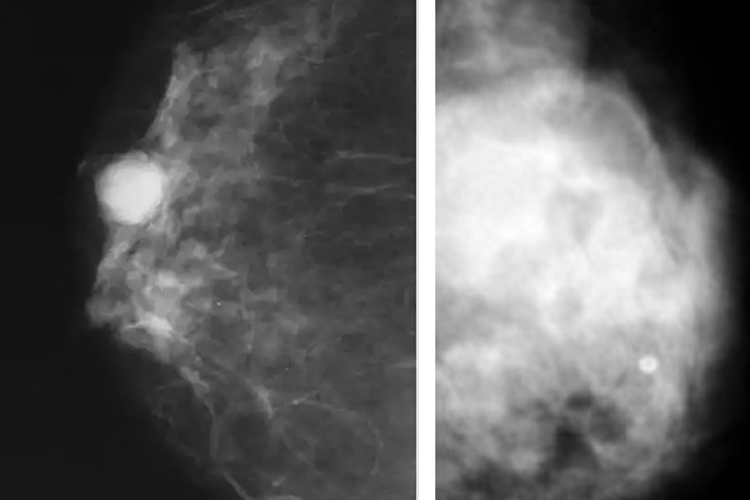

囊肿与肿瘤均属于体内异常表现,初期多数位于体内,体表症状不明显,难以用手触摸或肉眼观察进行区分,多需通过影像学检查辅助诊断。影像学检查通常提示囊肿有清晰边界,良性肿瘤边界清晰,而恶性肿瘤边界不明显,可为不规则形。囊肿为空腔形态,内含囊液或半流体物质,而肿瘤多为实质性肿物。随着疾病发展可观察两者的外观变化,通常囊肿改变较小或不发生改变,而恶性肿瘤可有明显增大,与周围组织分界不清。囊肿可能会随着发展有溢液的情况发生,如乳腺囊肿。